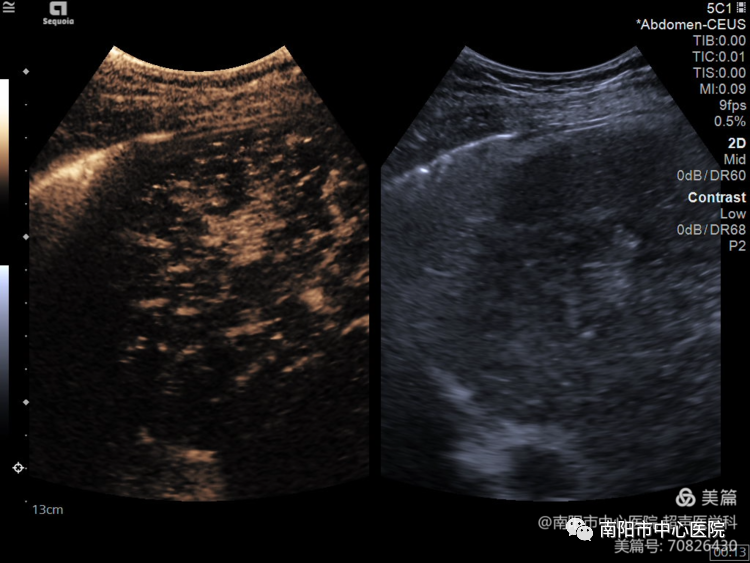

術(shù)前行超聲造影,可見腫瘤動脈期呈高增強,形態(tài)欠規(guī)則。

術(shù)后即時超聲造影,可見消融范圍約55*30mm,完全覆蓋腫塊,且超過腫塊范圍10mm安全邊界。